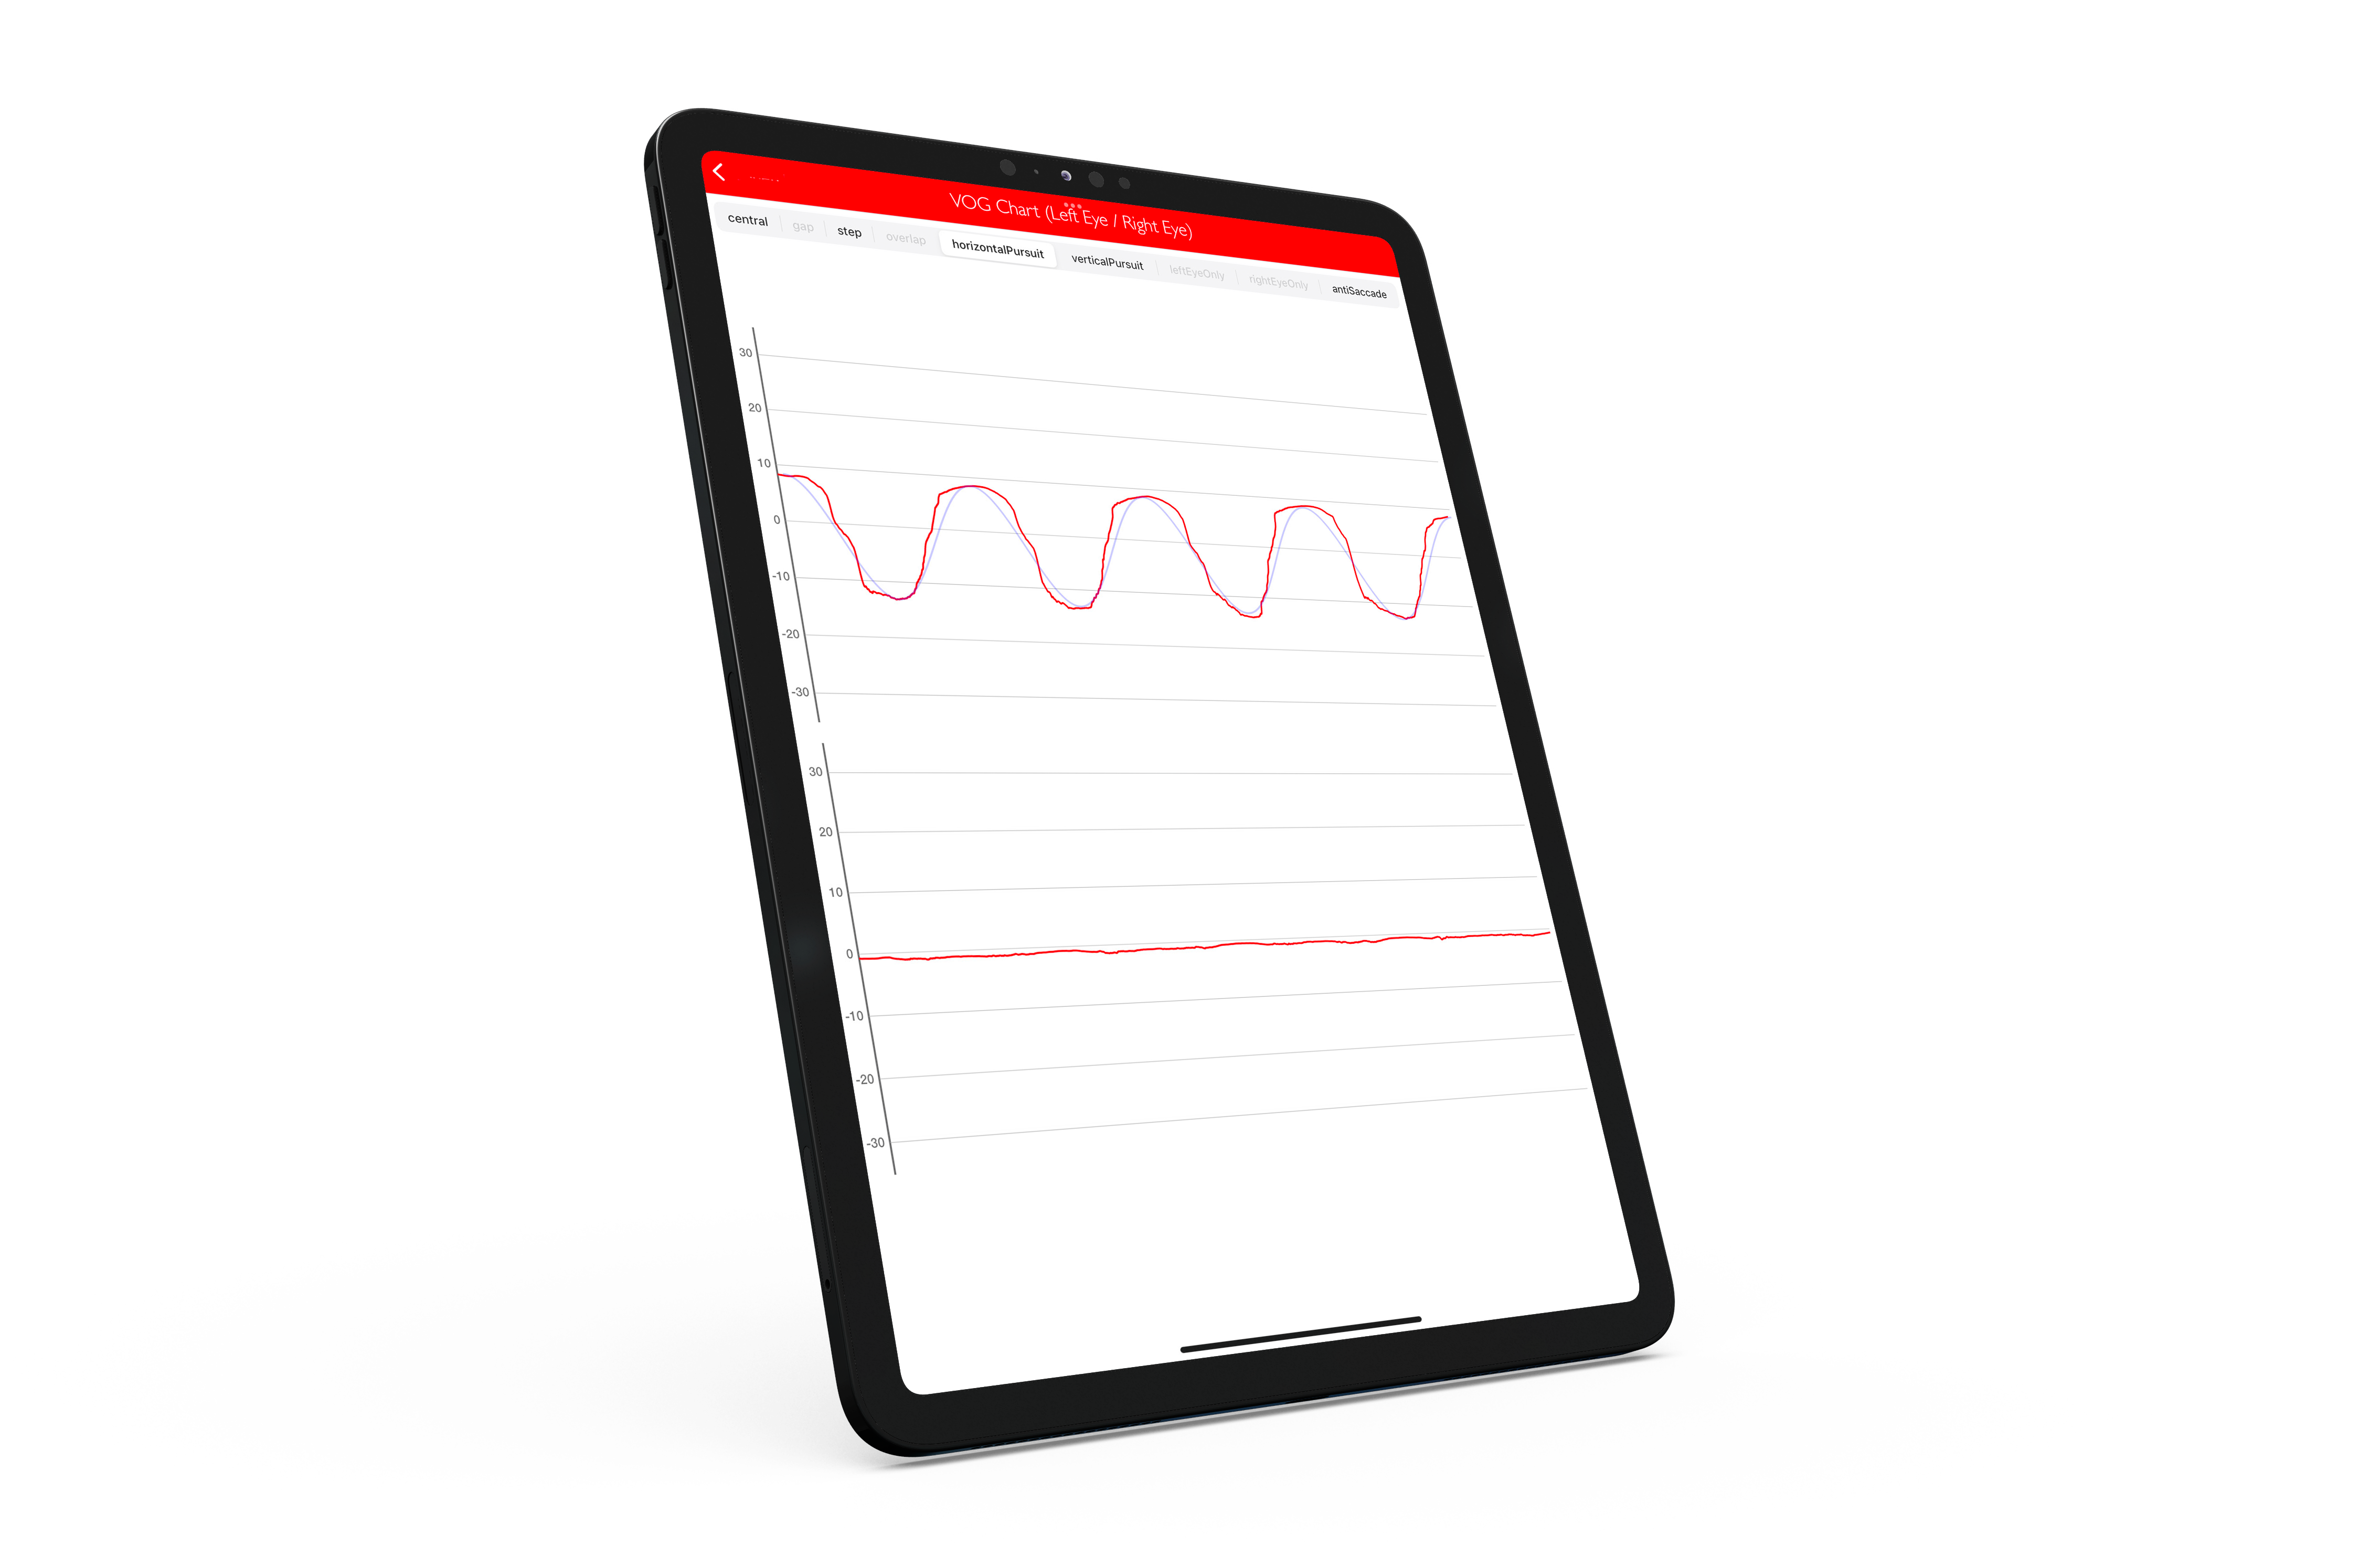

Perform an eye tracking exam in a few minutes just with an iPad.

We tested eVOG on a sample of patients and demonstrated it was able to distinguish reliably patients with eye movement abnormalities in comparison to the gold standard examination.

The apps require an iPad Pro running with iOS17 or later. For a high quality video oculographic examination, we recommend using a stand to maintain the iPad in the required position during the exam.